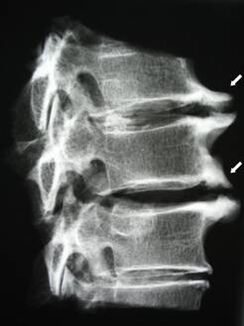

Dans les premiers stades, l'ostéochondrose est détectée par IRM. Plus tard, la pathologie peut être diagnostiquée par radiographie. Sur les radiographies de la colonne cervicale, une réduction de la distance entre les vertèbres, des modifications pathologiques des facettes articulaires et une ostéophytose sont perceptibles.